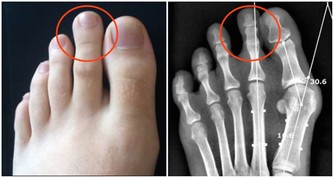

3、眼睛不適、無故流淚: 當人們切洋蔥的時,最先嗆到的是眼睛,然後是鼻子。眼睛是人體最敏感脆弱的器官之一,當外界空氣中存在刺激性分子,眼睛往往是最先感受到的。甲醛的一大危害就表現在對粘膜的刺激,甲醛屬於原漿毒物質,能與蛋白質結合,使眼睛感到刺激、乾澀、不適,甚至流淚。